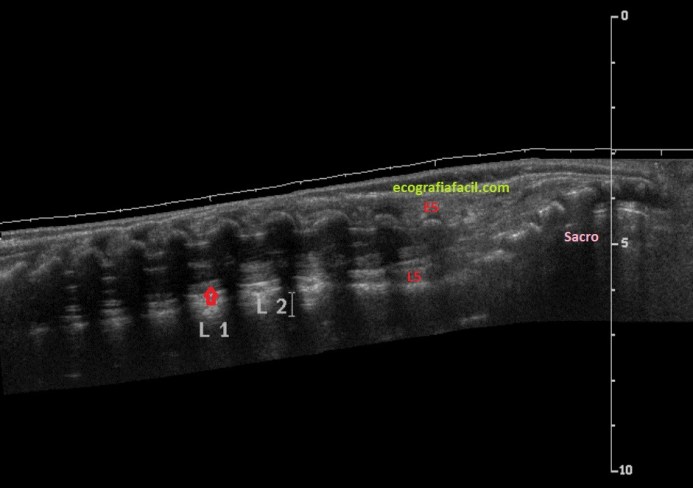

Para entender la imagen superior, compara con la normalidad:

En la imagen patológica observamos médula con dilatación de canal medular central en relación con hidrosiringomielia. Cono medular desciende hasta nivel de vértebras sacras, en porción posterior de canal espinal, anclada por un lipoma, que se extiende desde tejido graso subcutáneo a través de un defecto vertebral posterior en L5-S1, asociando también parte de meningocele a través de defecto.

In the pathological image we observed marrow with dilation of the central medullary canal in relation to hydrosyringomyelia. The medullar cone descends to the level of the sacral vertebrae, in the posterior portion of the spinal canal, anchored by a lipoma, which extends from the subcutaneous fat tissue through a posterior vertebral defect in L5-S1, also associating part of the meningocele through the defect.